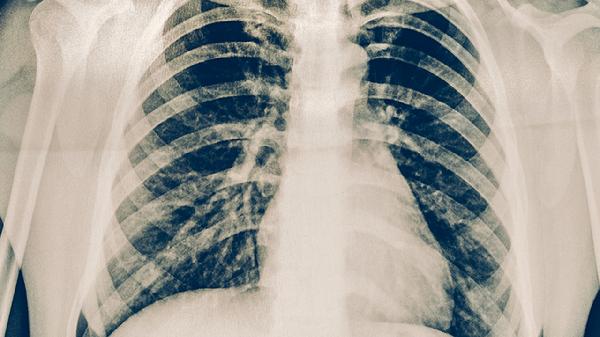

肺癌可能与长期吸烟、空气污染等因素有关,早期可能无症状,进展期可出现胸痛、咯血、消瘦等表现。确诊需通过胸部CT、支气管镜活检等检查。治疗方案包括手术切除、放疗、靶向治疗等。